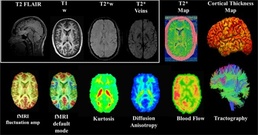

The initial part of the CARE study looked at the natural history, biomechanics, and neurobiology of acute concussion. The second phase, which is currently ongoing, looks at the intermediate effects of concussion and repetitive head impact over a college career. The third phase will investigate the long-term effects of concussions on members of the military and NCAA student-athletes.